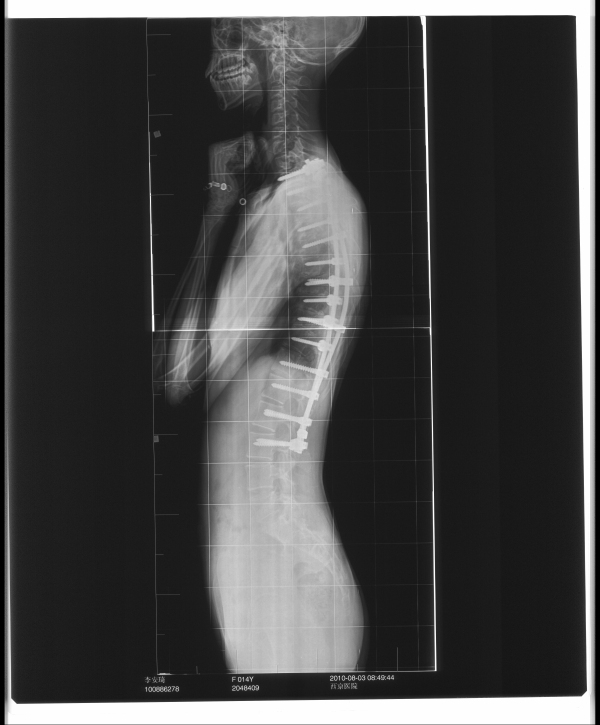

脊柱侧弯术后检查

术后神经诱发电位检测术中病人脊髓信号平稳无变化,术后安全返回病房。